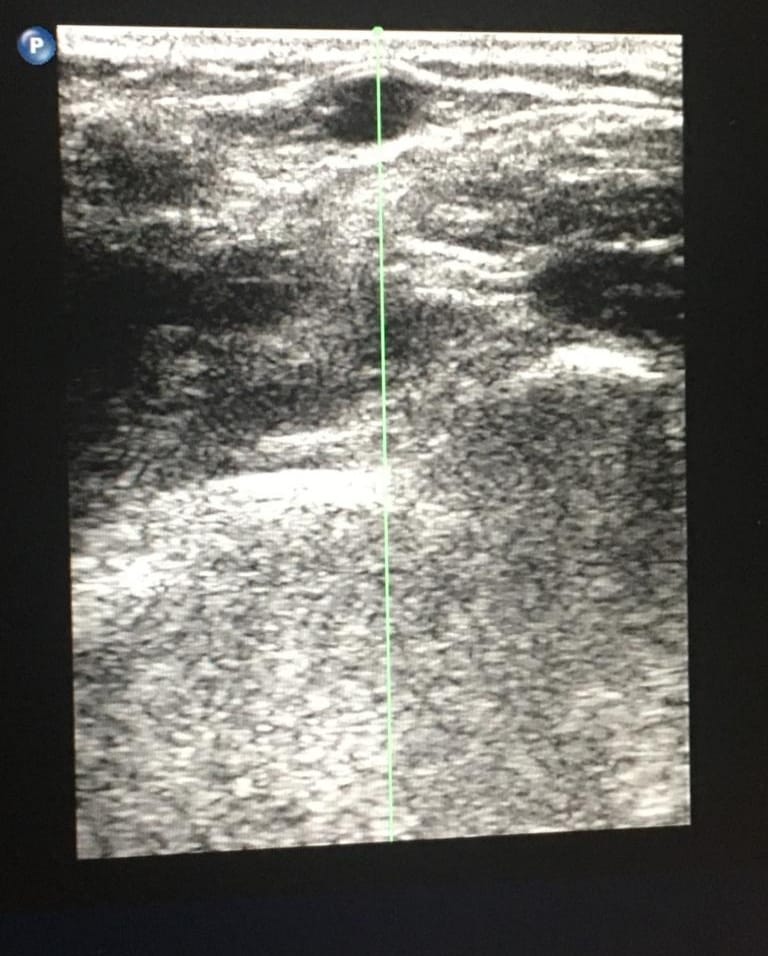

Entonces, ¿por qué seguimos pinchando los PICC en la flexura? Buena pregunta. Probablemente la respuesta esté en el desconocimiento del uso de la Ecografía, necesaria para acceder a las venas de la zona verde. Así, recurrimos a la fosa antecubital, lugar donde podemos visualizar y palpar las venas sin necesidad del ecógrafo… y donde hay más riesgo de complicaciones.

Por supuesto es imprescindible MEDIR el calibre de la vena que vamos a abordar «Mida la relación catéter-vaso antes de la inserción de un VAD de extremidad superior; asegurar una relación catéter-vaso de menos del 45%» INS 2021 , comprobar el trayecto ecográficamente, y NO pinchar con una vía periférica para luego canalizar el PICC (es una práctica común en algunos centros donde la aguja que incluye el set Arrow 7Fch tal vez no sea la más adecuada para acceder a venas del brazo, y más a femorales). Lo correcto es emplear el set de aguja específico (algunos de micropunción) que se incluye en los set PICC, que evitan lesionar en exceso los tejidos y además tienen materiales hiperecoicos para seguirlos de manera óptima en el ecógrafo.